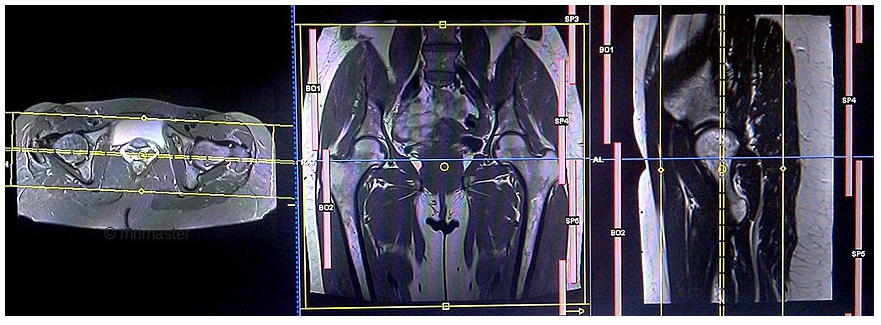

2. Chụp cộng hưởng từ khớp háng

Khớp háng là khớp có cấu trúc và chức năng phức tạp, bệnh lý liên quan khớp bao gồm chấn thương, tổn thương xương, Hoại tử khớp, viêm khớp, thoái hóa khớp, u... Có nhiều khảo sát hình ảnh cho các bệnh lý khớp háng. X quang thường là chỉ định đầu tiên. Chụp cắt lớp vi tính có giá trị đánh giá chi tiết cấu trúc xương, vỏ xương, nhưng chụp cộng hưởng từ khớp háng có vai trò đặc biệt quan trọng trong đánh giá các cấu trúc phần mềm cấu tạo nên khớp háng như: bao khớp, sụn khớp, các cơ tham gia vào vận động khớp háng, tủy xương....